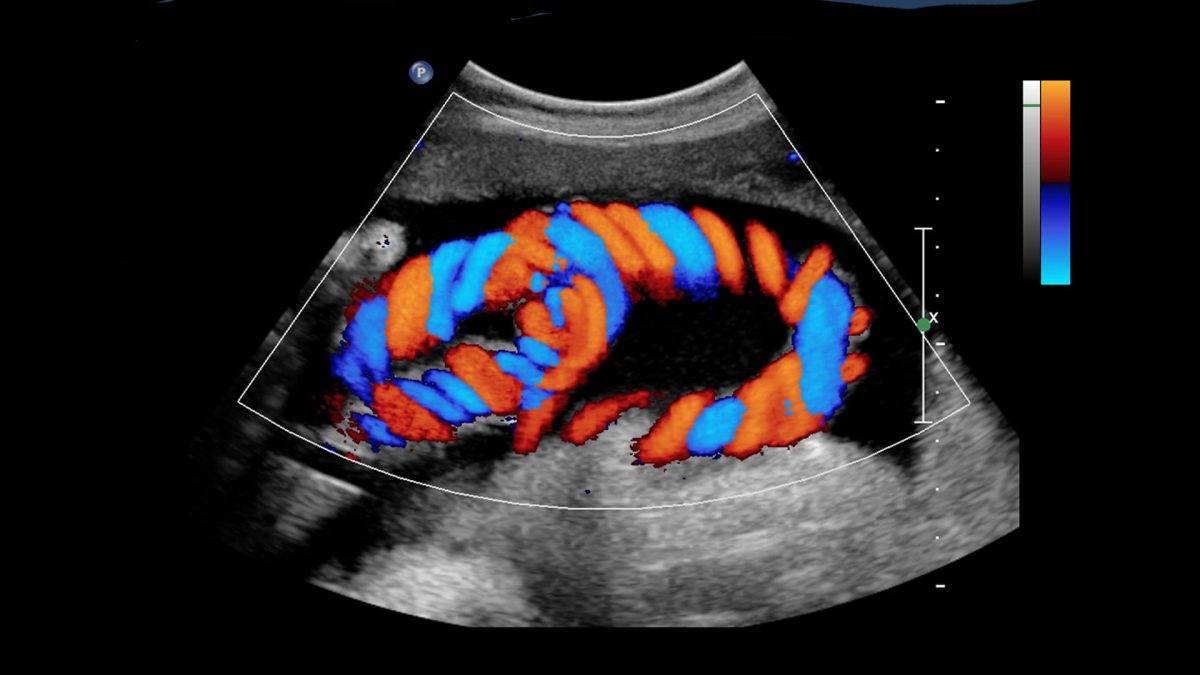

Renkli Doppler Neden Önemli?

81 ilden uygulanan renkli doppler birçok nedenler doğrultusunda önem arz eder. Uygulama profesyonel anlamda uygulandığından hastaların %100 memnun kalmasını sağlar. Renkli ultrason birçok hastalıkların hem teşhis hem de takip edilmesinde uygulanır. Bu nedenle yöntem geniş nedenler doğrultusunda uygulanır.

Renkli ultrasonlar doğrudan hastalıkların daha erken sürede ve şeffaf bir şekilde teşhis edilmesini sağlar. Bu nedenle de en çok başvurulan tanı uygulamaları arasında yer alır.

Renkli Doppler Nedir?

Renkli Doppler Hangi Alanlarda Kullanılır?

Renkli ultrasonlar da aynı şekilde checkuplar gibi birçok farklı alanlarda kullanılır. Uygulama daha çok kalp ve damar hastalıkları, anne karnındaki bebeğin sağlık durumu ve cinsiyetinin saptanması, çeşitli iç hastalıkları ve cinsel yolla bulaşan hastalık tespitinde uygulanır.

Renkli Doppler Hangi Hastalıkları Gösterir?

Birçok hastalıkları renkli doppler gösterir. Bu hastalıklar arasında çeşitli kalp ve damar hastalıkları, kas grubu hastalıkları birinci sırada yer alır. Pek çok riskli ve cinsel kanalla bulaşan hastalıkları da renkli ultrasonlar gösterebilir.